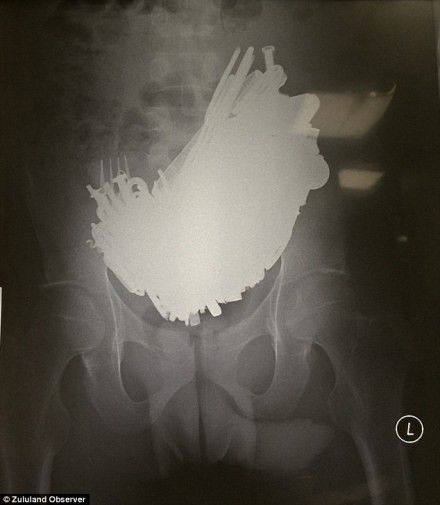

| Các vật kim loại trong bụng bệnh nhân này được các bác sĩ tìm thấy bao gồm cả tiền xu, dĩa nhà bếp, tuốc nơ vít... |

| Sau khi tiến hành chụp X-quang, nhân viên y tế tại bệnh viện Ngwelezana, Empangeni, 90 dặm về phía bắc của Durban, đã bị sốc khi nhìn thấy một mảng rộng lớn các mảnh kim loại khác nhau. |